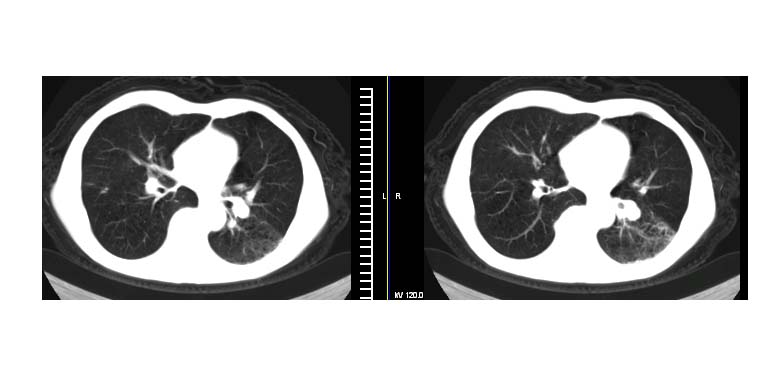

标题: CT11019:男性,66岁。发烧5-6天。治疗后无明显好转。 [打印本页]

标题: CT11019:男性,66岁。发烧5-6天。治疗后无明显好转。

斜肋积液

斜裂积液,炎症

明明是斜裂胸膜积液,为何都考虑阻塞性肺炎、肺不张(边缘内凹,而本例是外凸)。

以下是引用拾荒者在2007-12-24 19:47:00的发言:[br]明明是斜裂胸膜积液,为何都考虑阻塞性肺炎、肺不张(边缘内凹,而本例是外凸)。